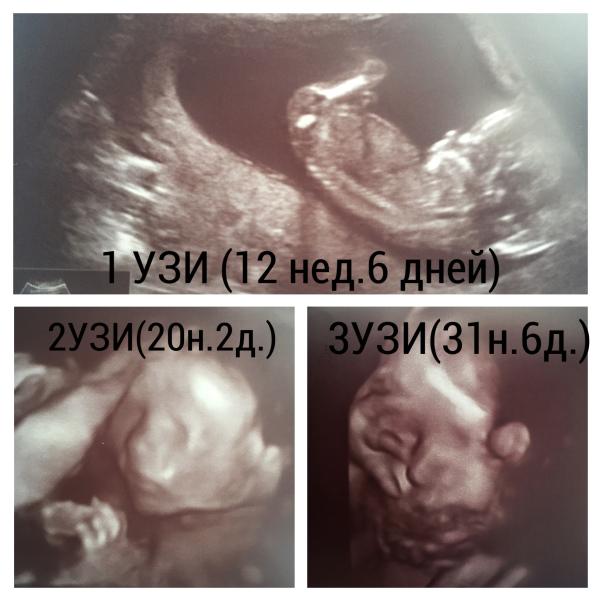

Сходили на последний скрининг🙌🏼как и два предыдущих делали у Саурского П.Н. 👨⚕️

Так как была только у него и бесплатно в жк! Могу сказать только по собственным ощущениям Саурский мастер своего дела👏🏻все досконально смотрит, измеряет, под разными углами смотрит, старается сделать удачные снимки малыша для мамы😻на 2 УЗИ моя крошка не хотела поворачиваться в профиль, так он нас отправил погулять и повторно принял, чтоб правильно измерить кость! После каждого приёма узнает остались ли вопросы, хотя до этого все рассказывает что видит и измеряет )нашёл общий язык с моим мужем, хотя он от всех этих процедур не в восторге)приём занимает примерно час, чуть меньше⏱

1 тоже есть 3д снимки) там просто совсем ничего не понятно)

А это у вас два последних узи это три д иди 4д!?